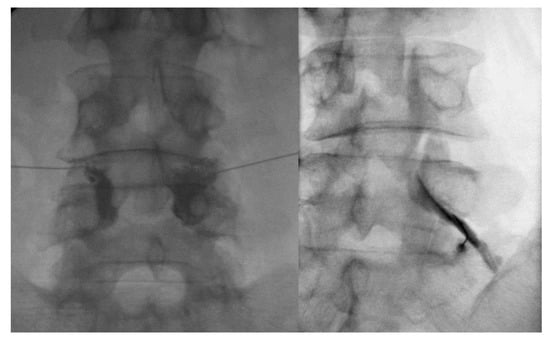

4.2. TFESI Procedure